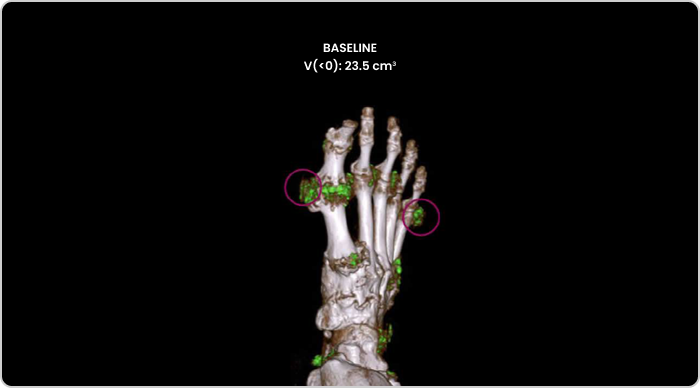

Dual Energy CT scan of uric acid buildup in foot at baseline

MIRROR RCT AT BASELINE

DECT image of urate buildup from a patient in MIRROR RCT.2

DECT, dual-energy computed tomography

The primary endpoint in MIRROR RCT was defined as the proportion of patients achieving and maintaining an sUA level of <6 mg/dL for at least 80% of the time during Month 6; 71% of KRYSTEXXA with methotrexate patients (N=100) vs 39% of KRYSTEXXA alone patients (N=52) met the primary endpoint (P<0.0001).3

Tophi resolution was a secondary endpoint that was defined as 100% resolution of at least one target tophus, no new tophi appearing, and no single tophus showing progression at Month 12; 54% (28/52) of patients receiving KRYSTEXXA with methotrexate achieved tophi resolution vs 31% (9/29) of patients receiving KRYSTEXXA alone (P=0.048).3,4